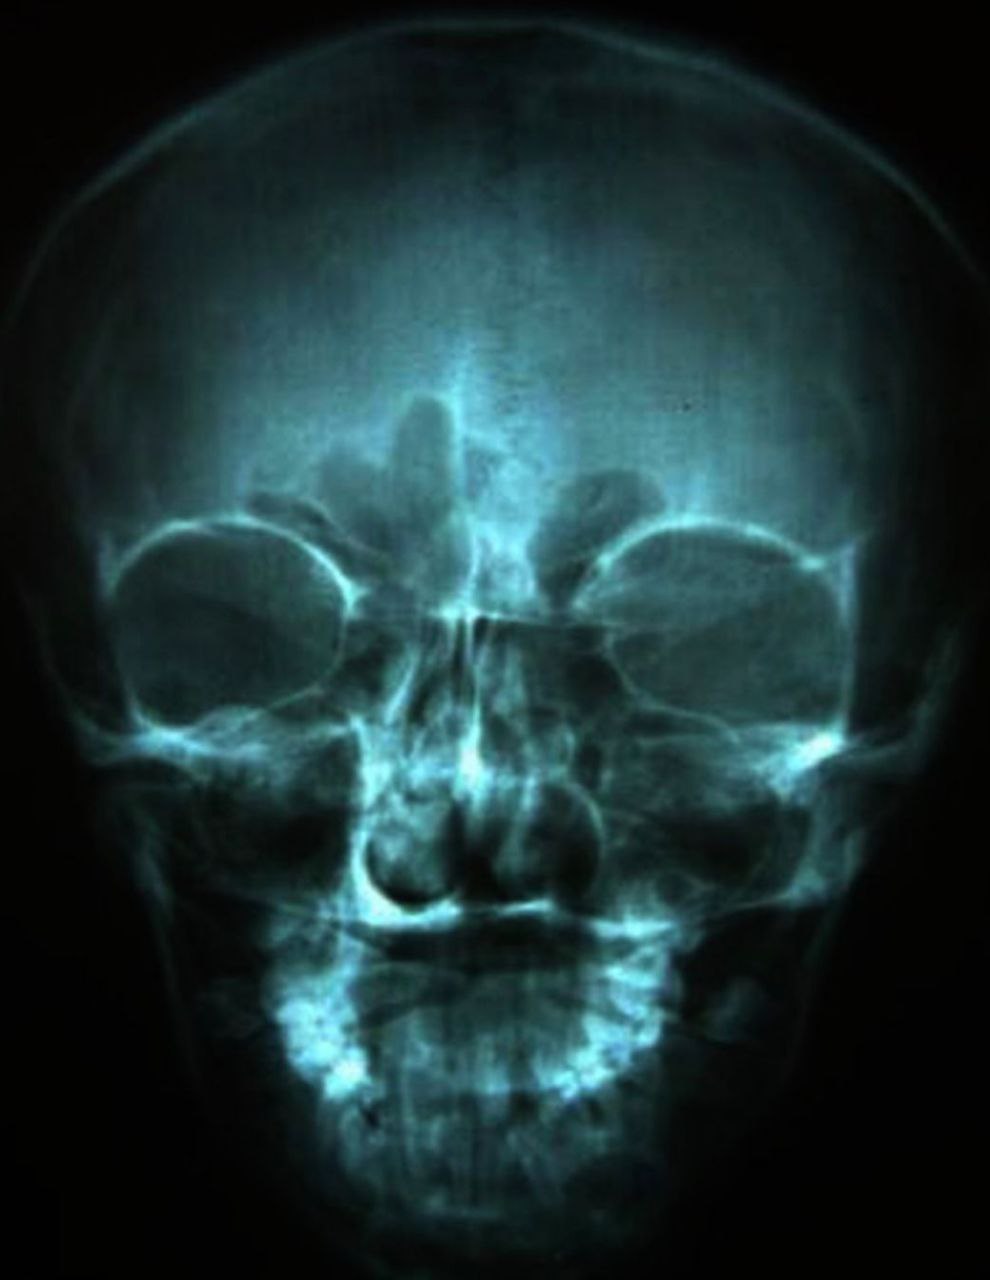

Diagnostic Images & Radiographs

Posterioanterior skull showing mandibular and malar hypoplasia with hypertrophy of both maxillary sinus walls.